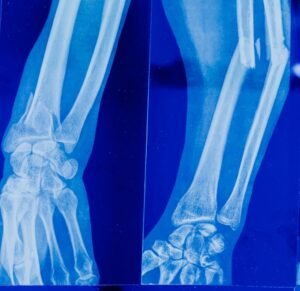

A ortopedia da mão é uma subespecialidade que trata lesões, doenças e deformidades que afetam mãos, punhos e antebraços. Com o uso constante das mãos no dia a dia, problemas como tendinites, fraturas, síndrome do túnel do carpo e lesões por esforço repetitivo (LER) são cada vez mais comuns.

A cirurgia da mão é indicada em casos em que o tratamento clínico não é suficiente para restaurar a função ou aliviar a dor. O procedimento pode envolver reparação de tendões, nervos, ossos, ligamentos e reconstruções complexas, muitas vezes com o uso da microcirurgia para resultados mais precisos.

Fraturas e Luxações

Atendimento ortopédico para traumas recentes, com foco em preservar a função e acelerar a recuperação.